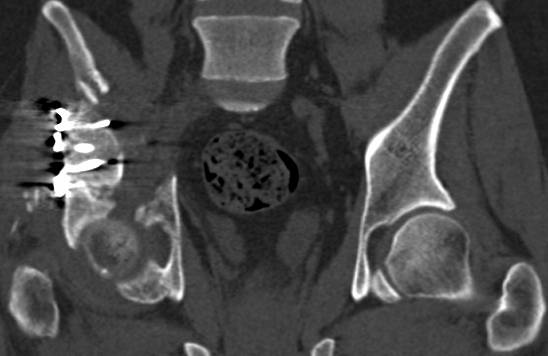

[Ortho] перелом правой половины таза

высылаю дополнительно  сканы.